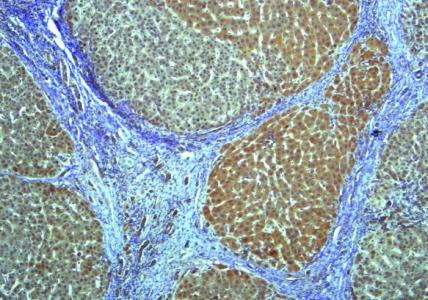

Pour les 300 millions d’adultes et d’enfants vivant dans le monde avec une stéatose hépatique non alcoolique, le développement d’une cirrhose du foie ou la formation de cicatrices, sont des facteurs importants de survie. Dans le cadre de cette étude menée chez des patients atteints de stéatose hépatique non alcoolique, leurs jumeaux et d'autres proches, cette équipe de l'Université de Californie San Diego trouve le moyen de diagnostiquer la cirrhose du foie simplement en analysant les microbes présents dans les selles du patient.

La cause précise de la stéatose hépatique non alcoolique est inconnue, mais l’alimentation et la génétique jouent un rôle important dans son développement. On pense que jusqu'à 50% des personnes obèses sont atteintes de stéatose hépatique non alcoolique, et les personnes ayant un parent au premier degré atteint encourent également un risque accru de développer la maladie. Dans une précédente étude auprès de patients atteints, l’équipe avait déjà découvert un schéma de microbiome intestinal distinguant la stéatose légère et modérée de la maladie avancée, ce qui leur permettait déjà de prédire quels patients étaient plus sévèrement atteints. Dans cette nouvelle étude, l’équipe a regardé si une lecture similaire du microbiome pouvait permettre de détecter la cirrhose.

Aujourd’hui, il est difficile et invasif de détecter une cirrhose du foie avant le stade avancé. Dans le but de pouvoir la détecter de manière plus précoce et plus simple, des chercheurs du Centre de recherche sur la stéatose hépatique non alcoolique du Center for Microbiome Innovation de l'Université de Californie à San Diego identifient des motifs uniques d'espèces bactériennes dans les selles des personnes atteintes. Bref, une signature pour un diagnostic plus facile. Or, être en mesure de diagnostiquer la cirrhose, c’est non seulement pouvoir mieux traiter les patients atteints mais aussi recruter les « bons » participants pour les essais cliniques et, en fin de compte, être en mesure de réduire le fardeau de la maladie. L’auteur principal, le Dr Rohit Loomba, professeur de médecine au Département de gastroentérologie de l’Université de San Diego, commente cette avancée : « la perspective d’un test non invasif des selles pour la cirrhose va contribuer à ouvrir la voie à d'autres diagnostics et traitements sur la base du microbiome notamment des traitements personnalisés pour un certain nombre de conditions ».

Les chercheurs ont analysé la composition microbienne d'échantillons de selles de 98 participants présentant une forme de stéatose hépatique non alcoolique et de 105 membres de leur famille au premier degré, dont des jumeaux. Ils ont séquencé le gène de l'ARNr 16S, un marqueur génétique spécifique des bactéries et de leurs quantités relatives dans les selles, entre autres. L’analyse constate que :

- 27 caractéristiques bactériennes uniques propres aux microbiomes intestinaux, et donc aux selles, sont identifiées chez les patients atteints de cirrhose avec une précision de 92% ;